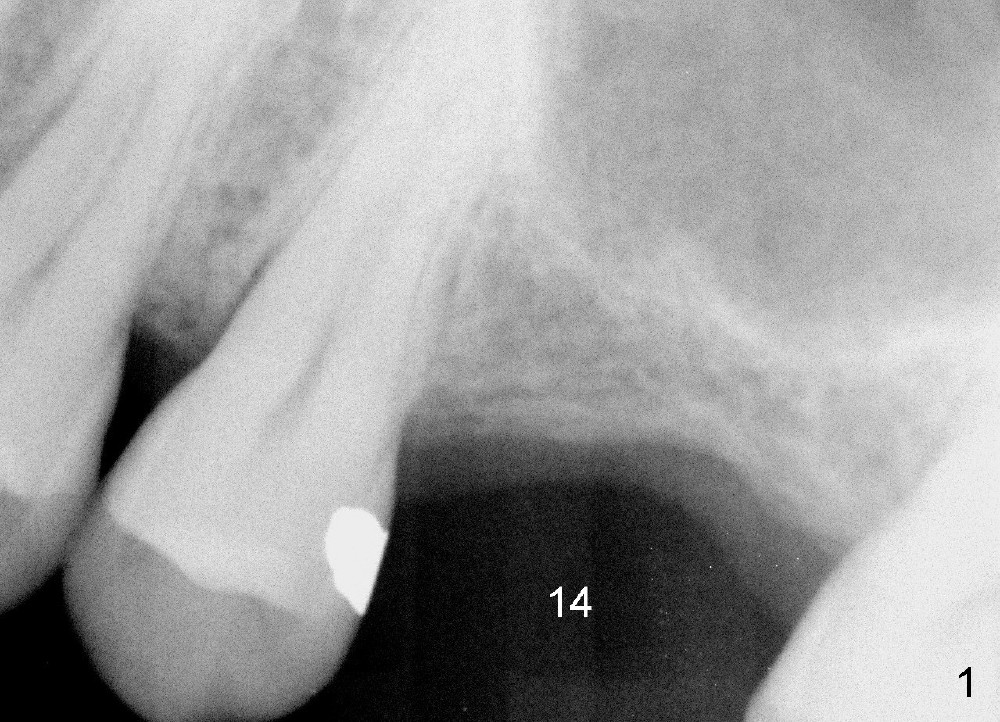

A 45-year-old man has lost the tooth #14 for a while (Fig.1); bone height is 5.4 mm. An extra wide and short implant is planned. Torus palatinus is large, suggesting that bone density should be high. A 6 mm tissue punch is chosen, but it is placed more palatal. If it were placed in the middle of the ridge, there would be no buccal keratinized gingiva (incision may avoid this issue). Additionally, the buccal portion of punch is made incomplete so that there is pedicle on the buccal side when the flap is raised (Fig.4,8: F). It is expected that the excess portion of keratinized tissue will form thick gingiva buccally. Osteotomy proves that bone is dense (Fig.2 (4.5x11 mm tap). Typical sinus lift is finished with placement of 6.4x6 mm (extra wide) bone-level implant (Fig.3, >55 Ncm). Following further torque, Fig.4 shows that the implant (I) is sub-gingival (<). Bitewings are taken to confirm that the implant plateau is at the crestal level (Fig.5,6 ^). PA shows sinus lift (Fig.7 *). The lingual aspect of the implant and healing abutment (H) is further bone grafted and covered by collagen dressing (Fig.8 *). The wound is protected with perio dressing. When the latter dislodges 7 days postop, the collagen dressing and bone graft are lost as well (Fig.10), while the buccal flap remains vital (Fig.9). The lingual exposed plateau should be able to heal normal. The collagen dressing should have been fixed in place by suture or as simple as a dental floss. There is mild nasal hemorrhage 1-2 days postop, possibly related to sinus membrane perforation and inability of Collagen Dressing to cover the perforation and contain the bone graft. When the patient returns for #9 implant placement in 3 weeks postop, the buccal flap reduces in size (Fig.11 *), while the palatal wound has healed with minimal exposure of the implant (Fig.12). Sinus graft remains in place 3 months postop (Fig.13); the buccal flap appears to have incorporated into a part of the gingiva (Fig.14). The bone density of the sinus lift appears to increase 10 days later when an abutment is placed (Fig.15 *). Although oral hygiene is pristine, there is apparent crestal bone resorption 12 months (Fig.16) and 20 months (Fig.17) post cementation, probably due to unfavorable crown/implant ratio and bruxism as well as pre-implantation bone loss (Fig.18,19). In contrast, an immediate implant in the same patient avoids pre- or post-implantation bone loss. In fact both the soft (Fig.20) and hard (Fig.21) tissues remain healthy 2 years 8 months post cementation. The sinus lift remains 3 years 8 months post cementation (Fig.22), while the crestal bone loss persists. The patients keeps complains of food impaction distal associated with bad smell 4 years 1 month post cementation. In fact the distal proximal contact is within normal limit. The bad smell is probably due to crestal bone loss (Fig.23 (pan), 24 (CT) *) and periimplantitis. Bone graft, PRF and Cytoplast membrane will be needed and fixed in place with long healing screw. When the patient returns for crown redo, he also reveals floss related gingival hemorrhage. There is pain associated with palatal sulcus probing with light gingiva erythema. Review of CT coronal section shows possible palatal (Fig.25 P) bone loss (*).